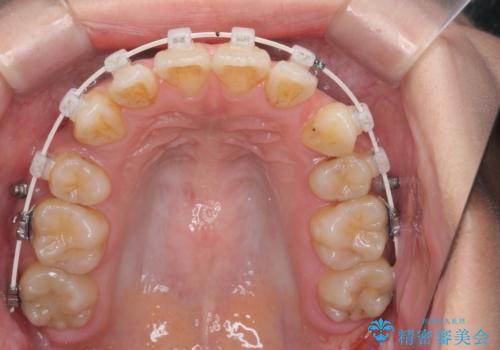

- 八重歯・がたつきのある歯並びの改善を求めて来院されました。

全部の歯が入り切るスペースがなかったため、小臼歯4本を抜去しワイヤーを用いたマルチブラケット矯正を選択しました。

歯並びの改善と共に、歯ブラシがしやすくなった!と喜んでいただくことができました。